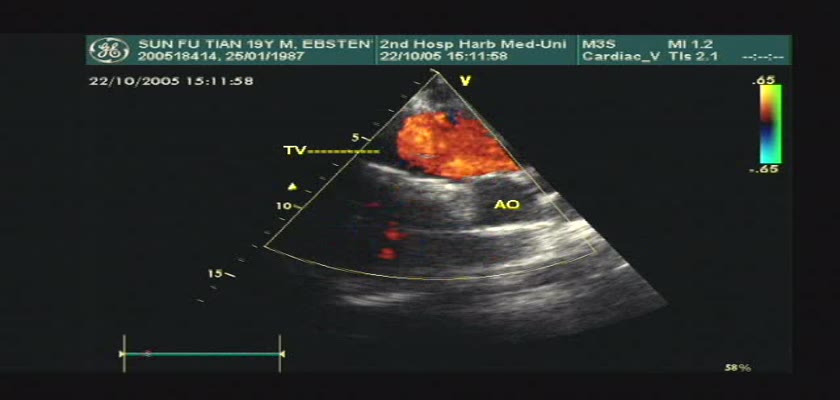

先天性心脏病超声诊断-先天性心脏病超声诊断视频17